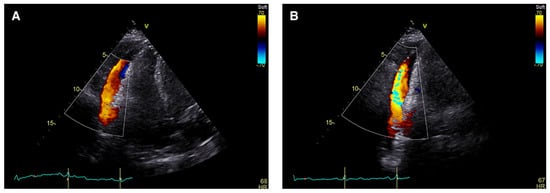

Transthoracic echocardiogram (TTE) confirmed a moderately sized circumferential serous pericardial effusion with no features of tamponade. Unusual prominent colour Doppler signals were seen within the pericardial space adjacent to the right ventricle free wall and directed towards the apex in systole (Figure 1, supplementary material: video clips). There was no evidence for communication with adjacent cardiac chambers. Flow signals were confirmed on pulsed-wave Doppler with maximal flow velocity of 100 cm/s. (Figure 2). Left ventricular dimensions and ejection fraction were normal while the right atrium and right ventricle were mildly dilated.

Figure 1. Transthoracic echocardiogram: apical 4-chamber view, colour Doppler signal within the pericardial effusion adjacent to the free wall of the right ventricle during ventricular systole.